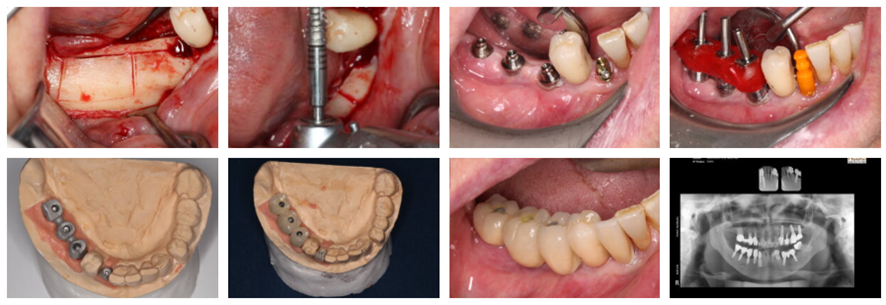

Para todas as situações clínicas

“A nova linha é excelente para implante imediato pós-extração. Venho utilizando sistematicamente nos casos de regeneração óssea guiada, principalmente nos aumentos verticais. Um diferencial é o fato desse implante possuir no topo uma parte de metal polido (0,25 mm de altura), sobretudo para casos de aumento vertical, onde não temos um controle de como e o quanto esse novo osso vai remodelar. Aliado a tudo isso, há a plataforma switching que tem como benefício afastar o microgap entre a conexão e o implante dos tecidos peri-implantares, minimizando as perdas causadas pelo infiltrado bacteriano e contribuindo para a estabilidade do osso marginal ao redor do implante.”

“A tecnologia do implante cone-morse Maestro (macrogeometria e plataforma switching) agora está presente nos implantes Hexágono Interno e Externo. Eu utilizo implante cone-morse, mas agora existe a possibilidade de utilizar os implantes de conexões hexagonais com maior segurança na osseointegração. A plataforma switching presente nos implantes HE e HI Switch permite, em algumas situações, que possamos inserir os implantes ligeiramente abaixo da crista óssea, beneficiando assim a formação óssea ao seu redor, protegendo o implante e respeitando o espaço para uma melhor neoformação do osso e do tecido mole.”